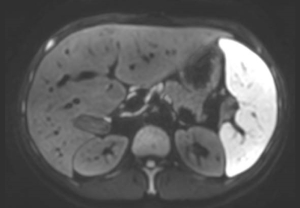

Niebywałe możliwości eliminacji szumów dostępne dzięki Philips SmartSpeed gwarantują wysoką rozdzielczość obrazów bez wydłużania skanowania. Jest to szczególnie istotne podczas obrazowania małych zmian chorobowych w układzie naczyniowym”.

Dr Takashige Yoshida,

Metropolitan Police Hospital w Tokio, Japonia